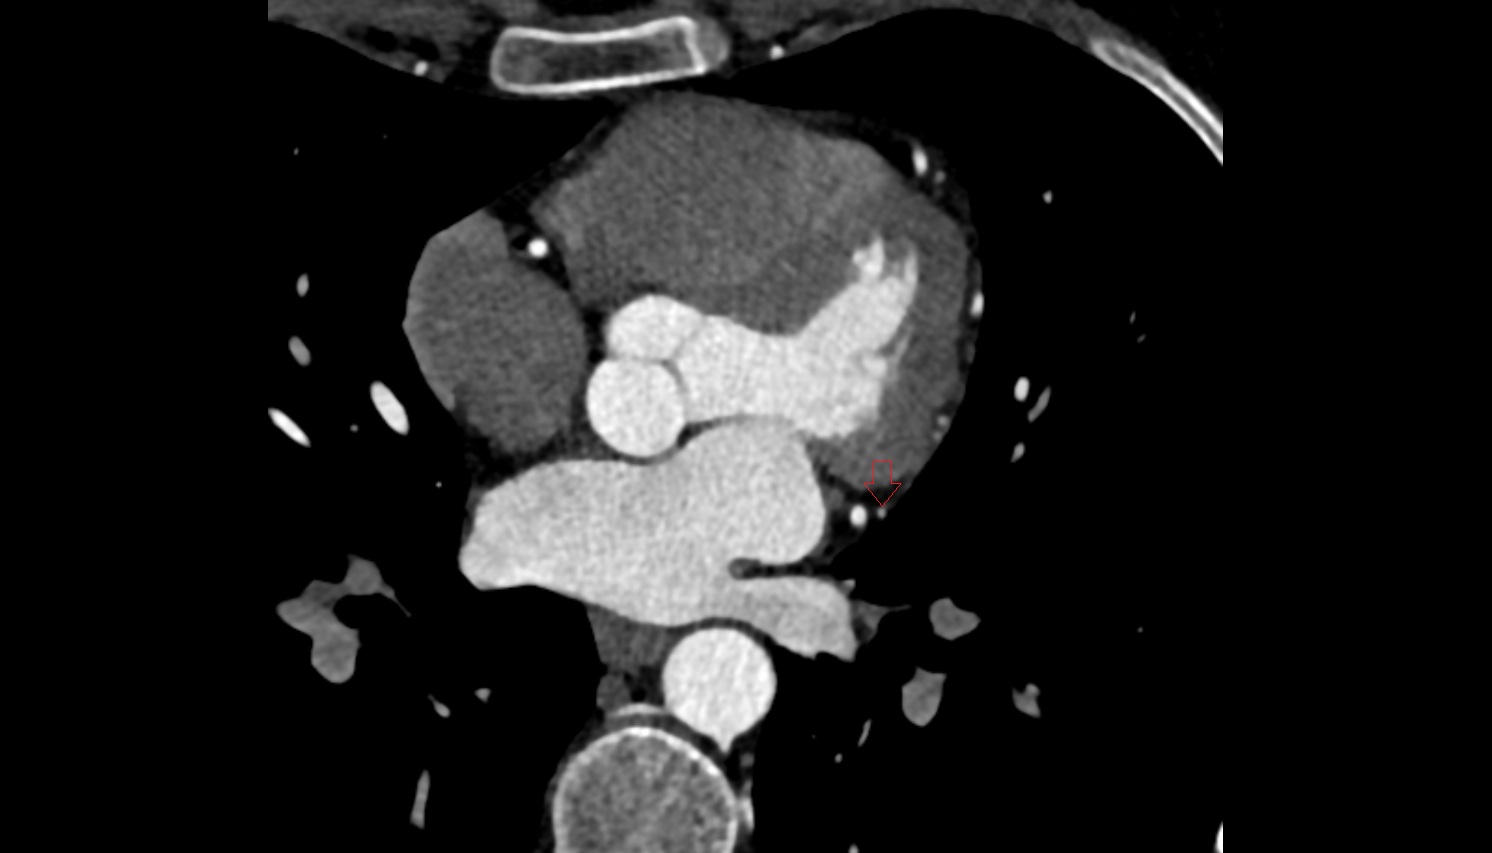

- Left anterior descending artery (LAD)

- Circumflex artery (LCx)

- Left main coronary artery (LMCA)

- Right coronary artery (RCA)